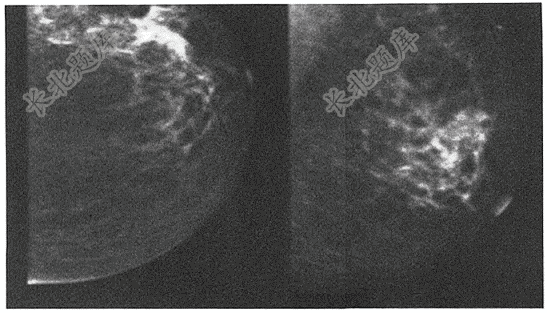

- 单项选择题患者,女,57岁,主诉“发现左乳肿块1周”,双乳对称,双乳无压痛,左乳触诊不满意,深部可疑结节,无乳头溢液。查左乳钼靶如图,最合适诊断为( )

A、纤维腺瘤

B、纤维囊性乳腺病

C、乳腺癌

D、乳腺炎

E、乳腺结核